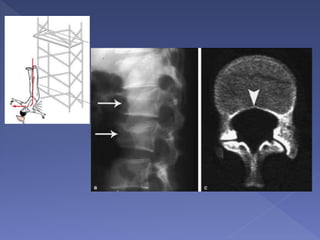

 burst fractures of the thoracolumbar junction

and lumbar spine

 classically occurs after landing on both feet or

buttocks following a fall from a height (lover's

fractures when associated with bilateral

calcaneal fractures)

 Rarely, due to seizure or electrocution

Mechanism –

 Axial compression of the vertebral body from above by the

nucleus pulposus, which explodes into the superior

vertebral endplate to result in centripetal displacement of

the body and its fracture fragments

 The retropulsion of the posterior aspect of the vertebral

body into the spinal canal is pathognomonic of a burst

fracture

 As the PLL is often intact, spinal traction can reduce this

displaced fragment by tightening the PLL

 Applying the three-column principle, there is a minimum

two-column disruption (the anterior and middle) in a burst

Determinants of Burst Fracture Instability

 Widened interspinous and interlaminar

distance

 Kyphosis >20 degrees

 Dislocation

 Vertebral body height loss greater than 50%

 Articular process fractures

 Posterior bowing of

the vertebral body

margin is diagnostic

of an axial

compression (burst)

fracture.